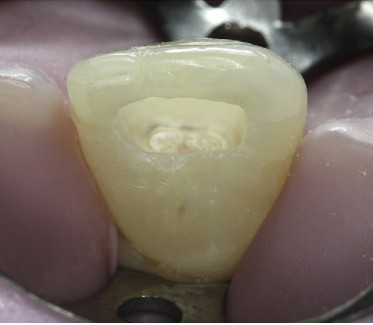

El recubrimiento pulpar directo es un procedimiento en el que se encuentra el agente de recubrimiento sobre el tejido que ha sido expuesto a los microorganismos y la inflamación está presente. La pulpotomía parcial, según lo descrito por Cvek , tiene un excelente pronóstico y consiste en la extracción aséptica, quirúrgica de la pulpa y la dentina expuesta que rodea la exposición a una profundidad de 1,5 a 2,0 mm, seguido del recubrimiento de la pulpa expuesta con un material adecuado. A diferencia de recubrimiento pulpar directo, el procedimiento de pulpotomía parcial crea un espacio para la colocación y la retención del material de recubrimiento pulpar.

El objetivo tanto del recubrimiento pulpar directo como de la pulpotomia es preservar la vitalidad pulpar para permitir el desarrollo continuo de la raíz, incluyendo el cierre del ápice radicular y el desarrollo de la dentina lateral radicular. El mineral trióxido agregado (MTA) ha demostrado evitar la penetración de bacterias y tiene un alto nivel de biocompatibilidad. Su uso ha sido recomendado para el tratamiento de las fracturas complicadas de la corona. Uno de los posibles inconvenientes de la utilización de MTA gris para la terapia pulpar vital en dientes anteriores es la pigmentación posterior de la corona. Por esta razón, el blanco MTA (WMTA) fue desarrollado. Aunque se ha demostrado que es comparable al MTA gris como un agente de recubrimiento pulpar, los informes muestran pigmentación por WMTA in vitro y en dientes in vivo, que se les aplico WMTA también se observó pigmentación coronal después de la pulpotomía.